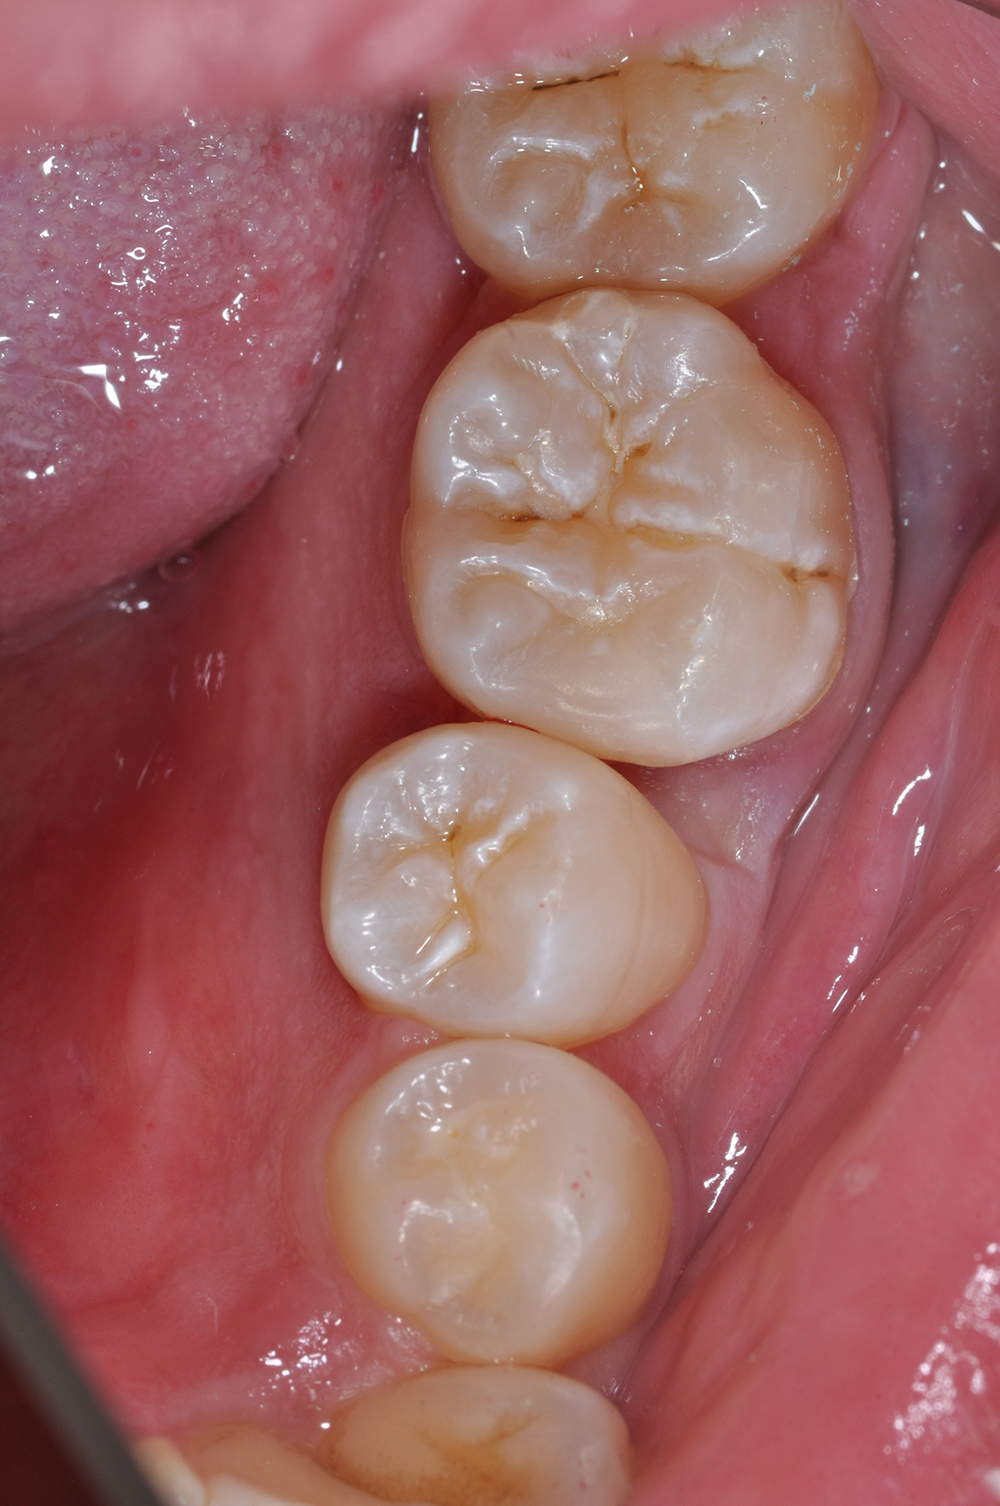

術前

術後

世代・性別

60代男性

主訴

歯ブラシで出血するので見てほしい

治療内容

ブラッシング指導、歯周基本治療、虫歯治療、根管治療、補綴治療

治療期間

6ヶ月

治療費

保険適応内

治療のリスク

治療後にしみる・痛みが出ることがある